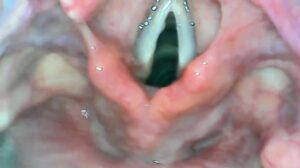

संतकबीरनगर के जिला संयुक्त चिकित्सालय में डॉक्टरों ने एक गर्भवती महिला का सफल ऑपरेशन करके एक मिसाल कायम की है। यह ऑपरेशन जनरल एनेस्थीसिया और मॉडर्न वीडियो लारिंगोस्कोपी तकनीक से किया गया, जो आमतौर पर सिर्फ बड़े चिकित्सा संस्थानों जैसे एसजीपीजीआई और आरएमएल में ही उपलब्ध होती है। यह मामला इसलिए चुनौतीपूर्ण था क्योंकि महिला के पीठ में बचपन में एक बड़ा ऑपरेशन हुआ था, जिससे उसकी रीढ़ की हड्डी में इंजेक्शन देना संभव नहीं था। ऐसे में, आमतौर पर मरीजों को बड़े अस्पतालों में रेफर कर दिया जाता है, लेकिन जिला अस्पताल की टीम ने मरीज को रेफर न करके इसी आधुनिक तकनीक का इस्तेमाल करते हुए सुरक्षित तरीके से सिजेरियन डिलीवरी कराई। ऑपरेशन करने वाली टीम में स्त्री रोग विशेषज्ञ डॉ. सीताराम कनौजिया और एनेस्थीसिया डॉ. संतोष त्रिपाठी शामिल थे, जिनके साथ सहयोगी स्वास्थ्य कर्मी गीता, शशि श्रीवास्तव और पंकज ने भी अहम भूमिका निभाई।